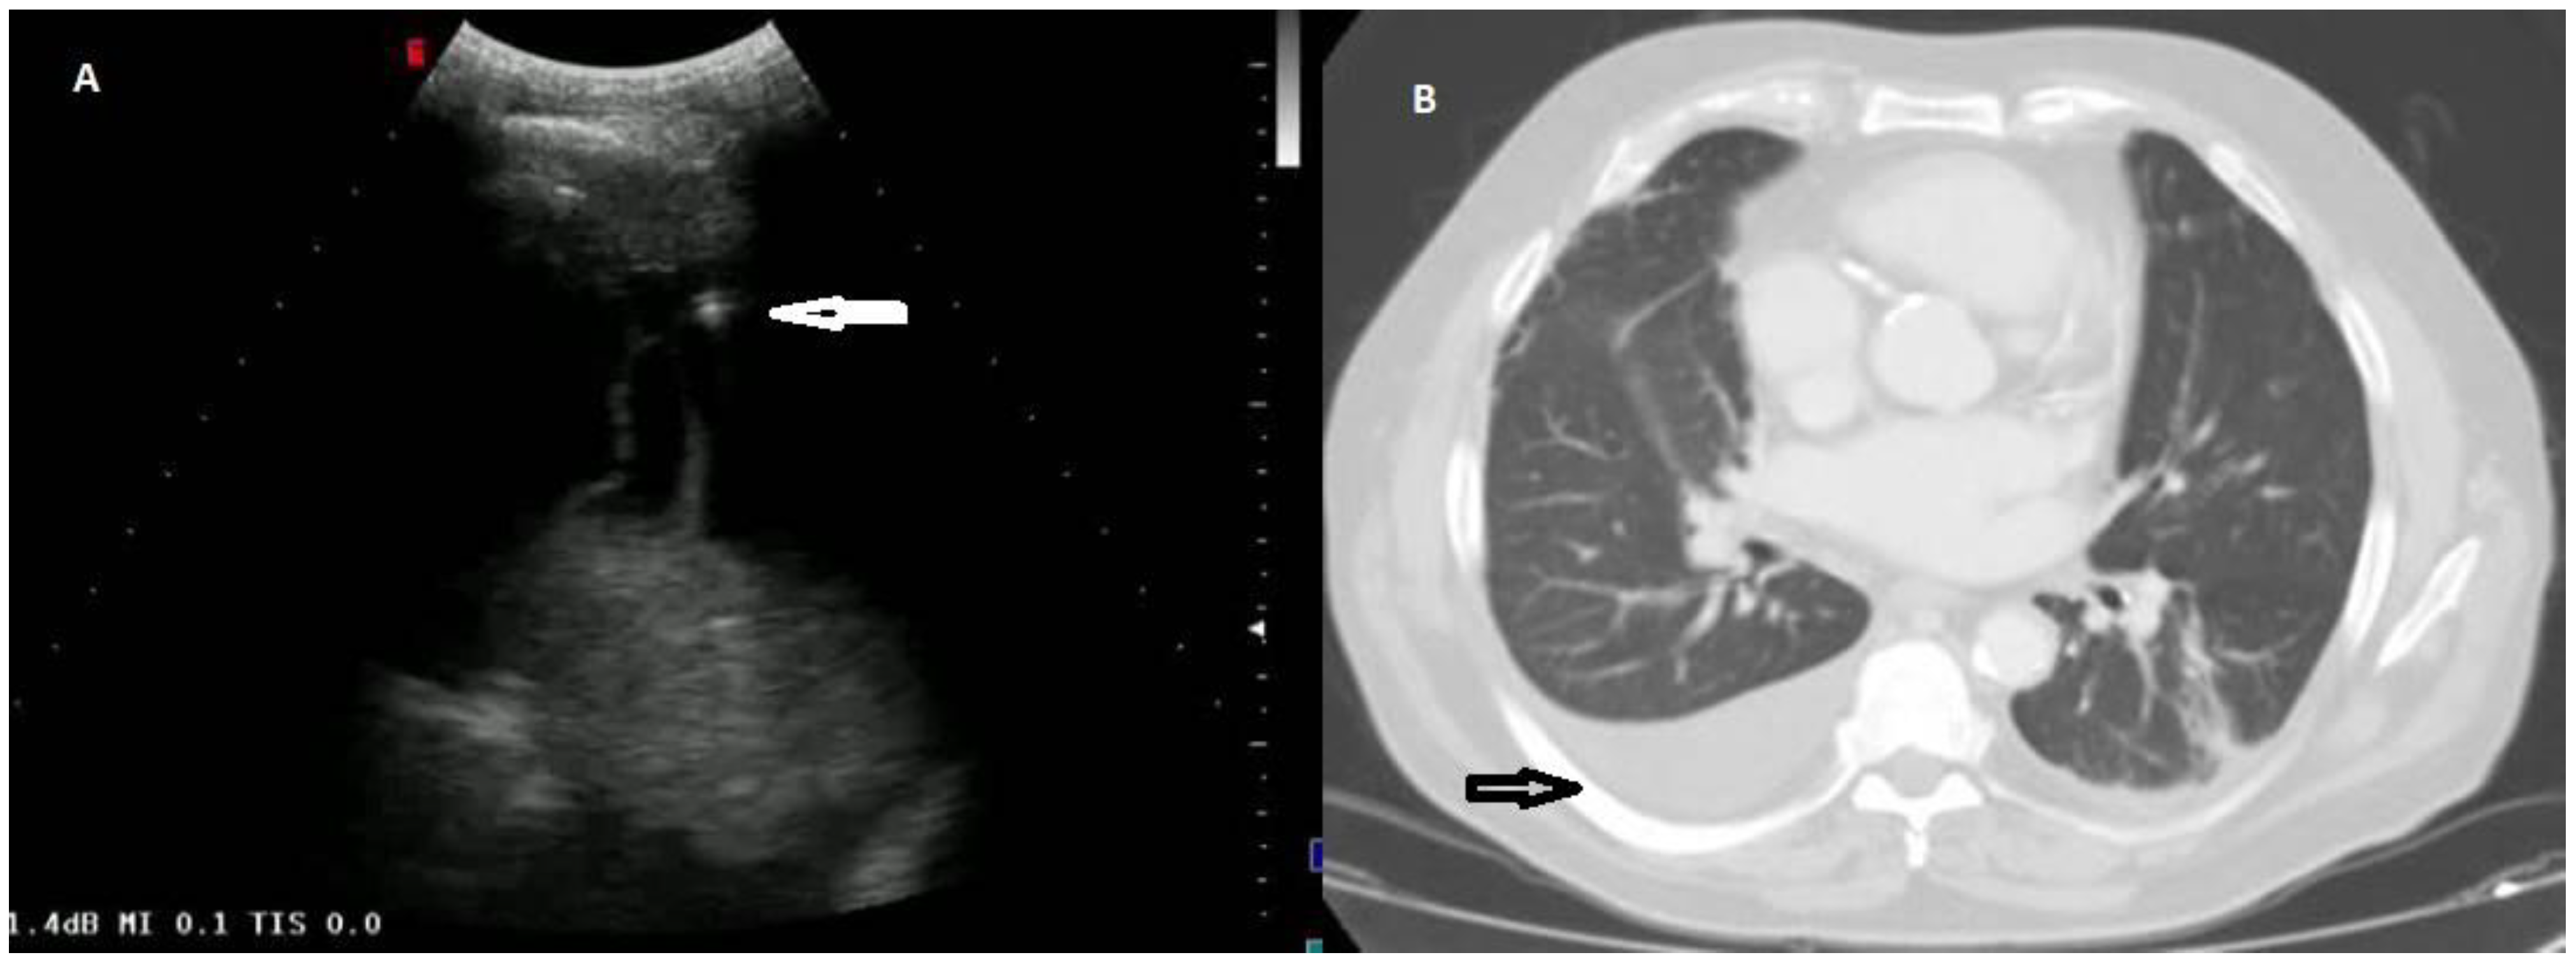

According to the macroscopic appearance, in 54 patients (14.96%) pleural effusion was hemorrhagic, in 297 (82.27%) citrine, and in 10 patients (2.77%) torbid. Based on the composition of the drained fluid, pleural effusions were classified as transudate in 27 patients (7.48%) and exudates in 334 patients (92.52%). On TUS examination, pleural effusions showed an anechoic appearance in 165 patients (45.71%), a heterogeneous ipo-iperechoic appearance (i.e., complex nonseptated) in 174 patients (48.20%), and a homogeneous hyperechoic appearance in 22 patients (6.09%). All the pleural effusion (100.0%) classified as transudates according to Light’s criteria showed an anechoic TUS appearance (Figure 2).

Only the exudative effusions showed a complex nonseptated or a hyperechoic TUS appearance. Considering the pleural effusions classified as exudates, the frequency distribution of the anechoic TUS appearance (n = 138/334, 41.32%) and of the complex nonseptated pattern (n = 174/334, 52.09%) were statistically higher than that of the homogeneous hyperechoic one (22/334, 6.59%), with a p-value < 0.0001. The number of complex nonseptated exudates was statistically higher compared to that of the anechoic ones (p = 0.005) (Figure 3).

Figure 2. (A) TUS scan showing an anechoic effusion with consensual parenchymal atelectasis during thoracentesis with a multifrequency convex probe (3.5 MHz). The tip of the needle is highlighted by a white arrow. (B) The corresponding CT scan shows a smooth thickening of the peribronchovascular interstitium and a bilateral pleural effusion with passive atelectasis of lower lobe in the right lung (black arrow).